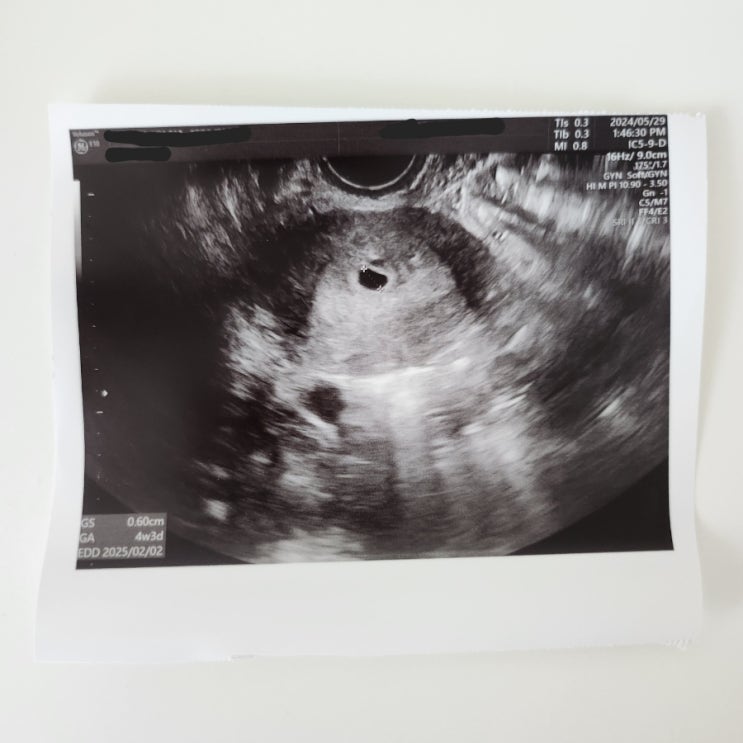

서울역 차병원 시험관 임신 5주차/6주차 초음파, 난황이랑 심장소리듣기 / 입덧약 의료보험 적용!!

두근두근 일주일이 드디어 지나고 다시 병원가는 날이되었어요. 왜이렇게 일주일이 안가는지ㅠㅠ 아기는 잘...

서울역 차병원 시험관 동결 5일배양 이식 12일차 1차피검 / 14일차 2차 피검 / 높은수치 임테기 진하기 + 아기집을보다!!

1차 피검 이식 12일차 아침에 한 임테기!! 엄청 진하다...!!! 이제는 소변 닿자마자 선이 생기기 시작해요....